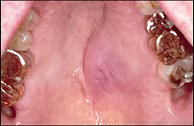

Non-Ulcerated Mass of the Hard Palate

A 66-year old white male presented with a raised lesion on the left hard palate. The patient had been aware of the lesion for approximately two weeks, and there was no history of recent or past trauma.